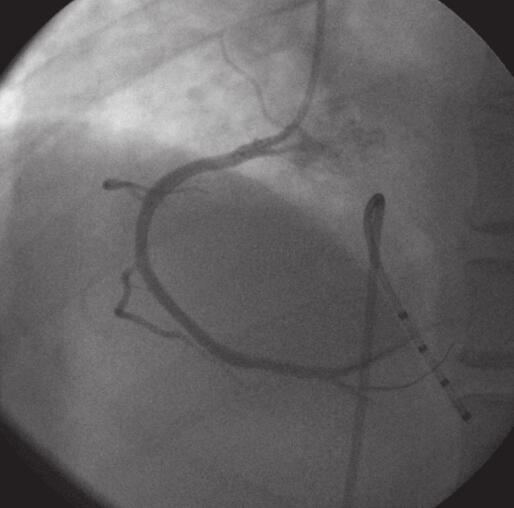

1小时条评论余times;,男,62岁,因反复胸闷、胸痛2年,伴呼吸困难,加重1+小时入院。2年前,活动后(爬坡)出现胸部闷痛,发冷,伴呼吸困难,多汗,且进行性加重,无黑蒙、晕厥,无端坐呼吸,无双下肢水肿,休息后很快好转,自服硝酸甘油后也可好转。1+小时前,无明显诱因出...